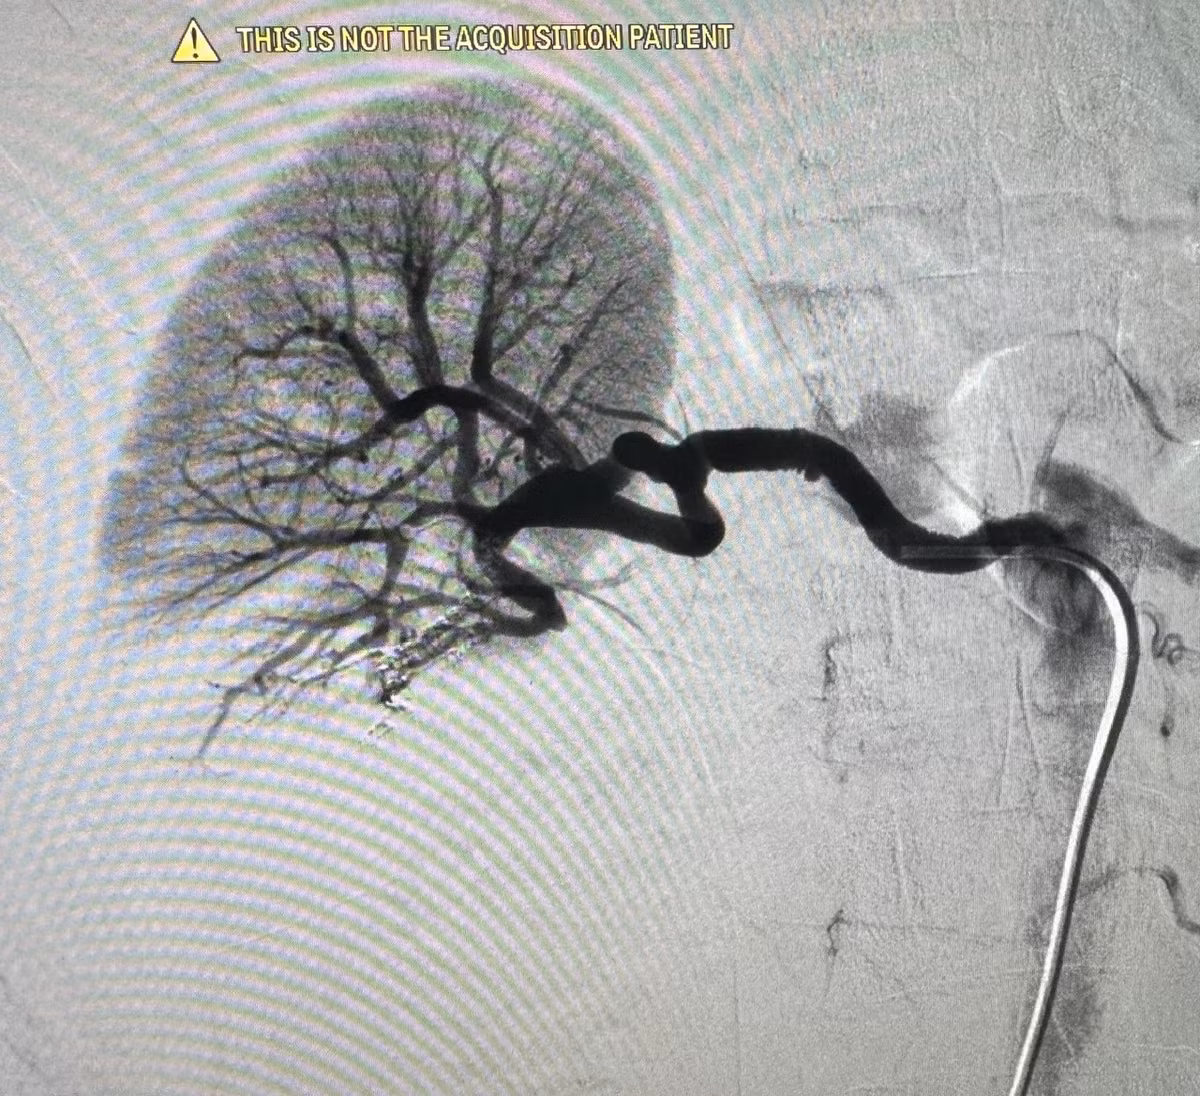

1h sáng ngày 14/7, tại phòng can thiệp – Bệnh viện Đa khoa Hùng Vương, các bác sĩ Khoa Chẩn đoán hình ảnh phối hợp Khoa Hồi sức cấp cứu đã nút mạch cầm máu thành công cho nam bệnh nhân 59 tuổi bị vỡ thận độ IV do tai nạn giao thông nghiêm trọng.

Hình ảnh CT ổ bụng ghi nhận: Vỡ thận phải độ IV; Chảy máu hoạt động; Tụ máu quanh thận. Đồng thời, bệnh nhân còn vỡ xương sọ và xương mặt.

Trong tình huống nguy kịch, bệnh nhân đã được can thiệp nút mạch ngay trong đêm tại Bệnh viện Hùng Vương. Nhờ xử trí kịp thời, các bác sĩ đã kiểm soát chảy máu, bảo tồn tối đa nhu mô thận và giành lại sự sống cho người bệnh. Hiện bệnh nhân đang tiếp tục được theo dõi sát tại Khoa Hồi sức cấp cứu.

Ca can thiệp trong đêm cho bệnh nhân - Ảnh BVCC